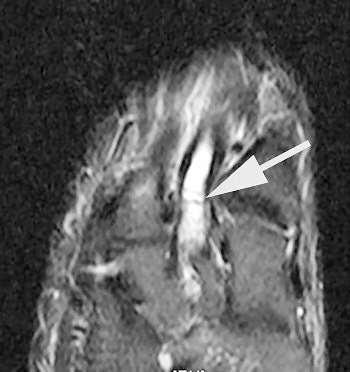

| Delayed image shows increased bone marrow edema and fracture line, base of second metatarsal. |

The follow-up study was led by Dr. Nancy Major, associate professor of radiology at Duke University Medical Center's musculoskeletal division. Her study determined that MRI can effectively predict metatarsal stress fractures by depicting bone marrow edema (a precursor to fractures), thereby enabling the prevention of potential fractures with the use of orthotics.

In this study, 26 male basketball players from Duke and North Carolina Central University in Durham were imaged before and after their 2003 season. Although 19 of 52 feet showed abnormalities with MRI, only one player had complaints of a symptomatic midfoot. The use of an orthotic provided immediate relief, and the player did not subsequently develop stress fractures.

A player experiencing no symptoms, however, did develop a metatarsal stress fracture before he could be fitted for an orthotic ("The role of imaging in the feet in asymptomatic collegiate basketball players," RSNA meeting, December 2, 2004).